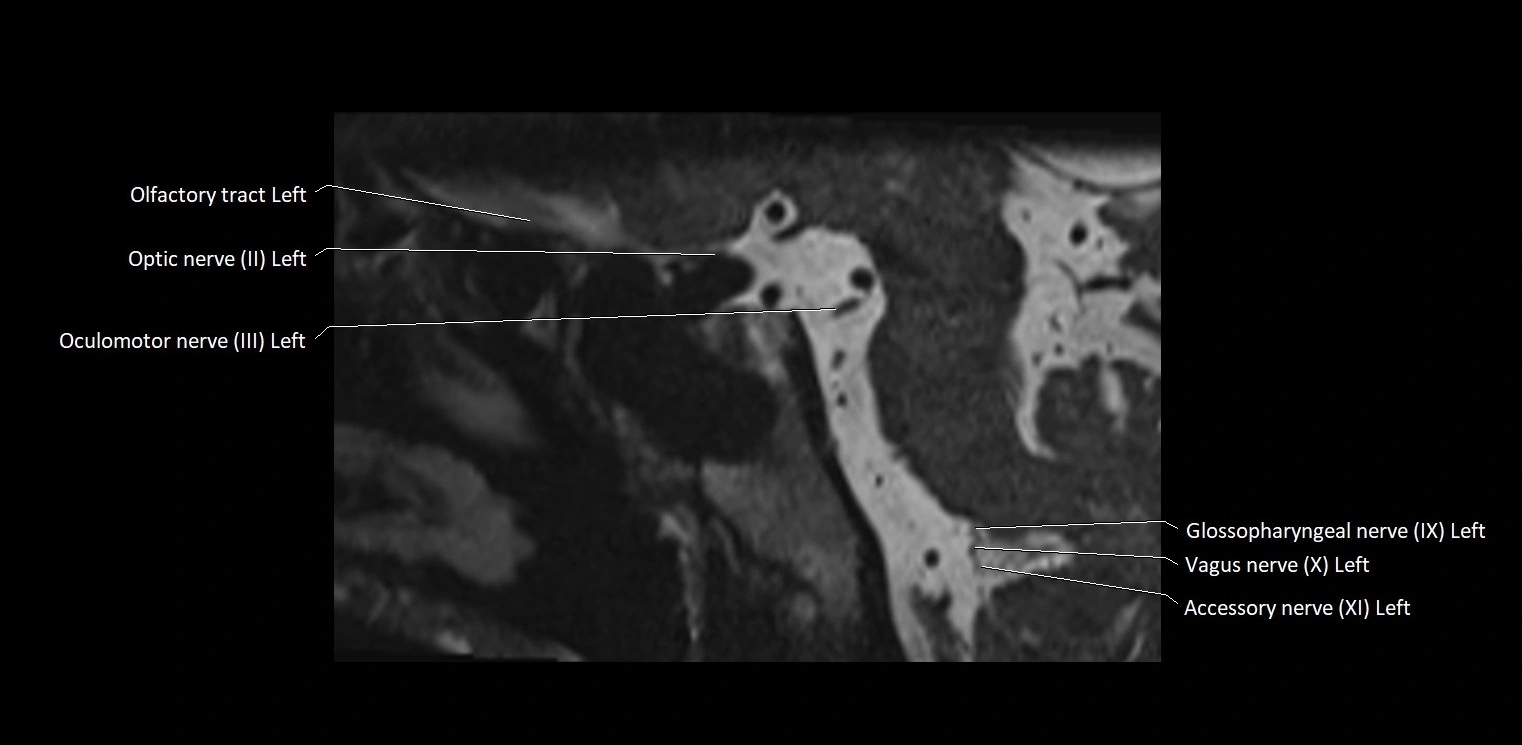

MRI Appearance

• The abducens nerve is a small, thin, linear structure

• Best visualized on high-resolution T2-weighted 3D MRI sequences (e.g., FIESTA or CISS)

• Seen as a hypointense (dark) line running from the brainstem at the pontomedullary junction, traversing the prepontine cistern, and entering Dorello’s canal under the petrosphenoidal ligament, then into the cavernous sinus, and finally the orbit

• May be challenging to visualize in standard MRI due to its small size

• Pathology may be inferred by absence, displacement, or enhancement of the nerve

MRI images

image